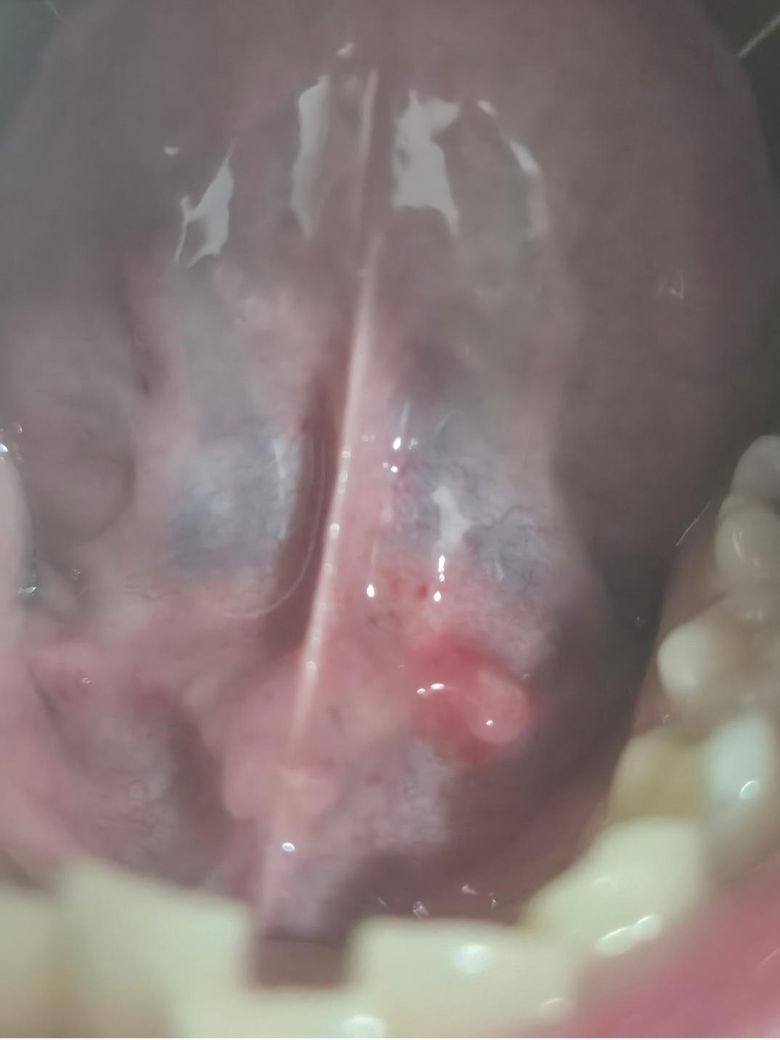

자고 일어났더니 혀 밑에 뭔가 생겼어요.

이거...뭔가요? 그리 막 아프지는 않은데 크기가 좀 커 보여서 걱정이 되네요. 병원을 가야할까요? 만약 간다면 어떤 과로 가야 할까요?

사진으로는 정확한 진단 불가능하며 병원 방문하셔서 직접 육안으로 진료 보셔야 합니다

혀 밑에 염증이 생긴 경우는 일반적으로 타액선 염증이나 타액선 낭종이 원인일 수 있습니다. 염증이 생기면 부기, 붉어짐, 통증 등이 발생할 수 있으며, 입안이 건조하거나 맛이 이상할 수 있죠. 염증이 심해지면 고름이 생길 수도 있구요

이런 경우에는 이비인후과나 구강내과에서 진료를 받는 것이 좋습니다. 염증의 원인을 확인하고, 필요에 따라 항생제 치료나 염증을 완화할 수 있는 처방 받으시면 될듯해요